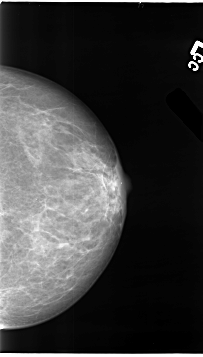

B_3101_1.LEFT_MLO

LEFT_MLO LINES 4744 PIXELS_PER_LINE 2792 BITS_PER_PIXEL 12 RESOLUTION 50 NON_OVERLAY